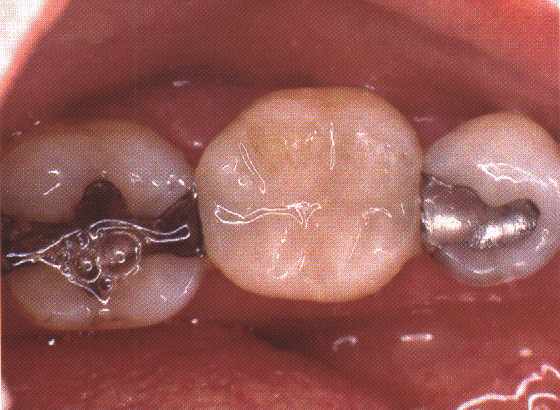

Een rubberdam - ook wel cofferdam genoemd - is met behulp van een klem en draadjes over de kies bevestigd. Het aangetaste materiaal is al uit de kies verwijderd.